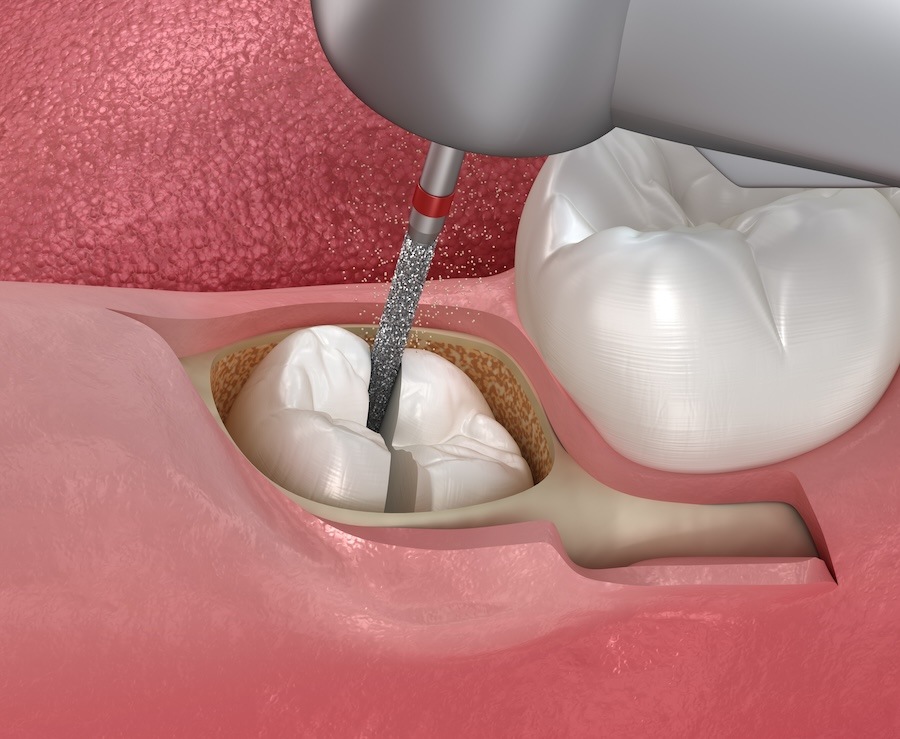

Wisdom Tooth Removal in Singapore: Surgical Extraction Explained

Wisdom tooth removal is a common dental procedure in Singapore, especially among young adults and working professionals. While some wisdom teeth can be removed through simple extraction, many cases require a more complex approach known as surgical extraction. This method is typically necessary when the wisdom tooth is impacted, partially erupted, or positioned in a […]